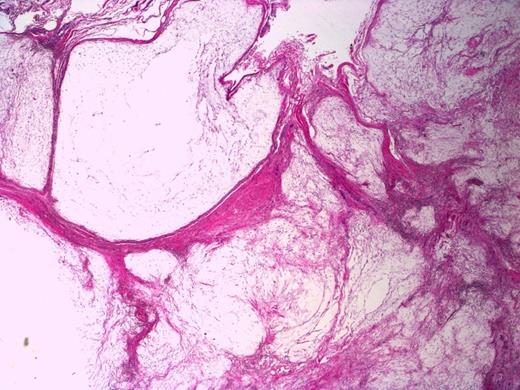

Multicystic appearance of the lesion with fibrous septa. H&E stain, 20X magnification